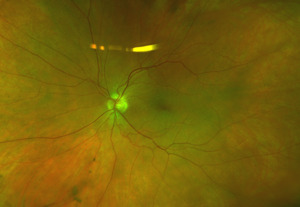

On posterior segment evaluation, the optic nerve head appeared well perfused, with normal cupping in both eyes; the maculas appeared flat and avascular. Several cotton wool spots were evident in the posterior pole, concentrated near the optic nerve head, greater in OD than OS, as seen in fundus photographs of the posterior pole (Fig. 1 & Fig. 2). There was no evidence of diabetic or hypertensive retinopathy. No other signs of pathology were found in posterior pole and periphery of either eye.

Spectralis optical coherence tomography of the macula demonstrated no evidence of macular edema in either eye. However, a line scan through the cotton wool spots showed focal thickening of the retinal nerve fiber layer (Fig. 3). Optos fluorescein angiography was normal and demonstrated no evidence of non-perfusion or leakage within posterior pole and peripheral retina (Fig. 4 & 5).

After consulting with a retinal specialist, the patient was confirmed to have bilateral cotton wool spots that were likely due to a recent COVID-19 infection based on the ability of the virus to infect the vascular endothelium or produce the release inflammatory cytokines.4 The plan was for the patient to return for a follow-up examination in three months including a dilated fundus exam. At the follow-up visit three months later, the cotton wool spots were fully resolved, and the patient was instructed to return for an annual eye examination unless new concerns developed. (Fig. 6 & Fig. 7)